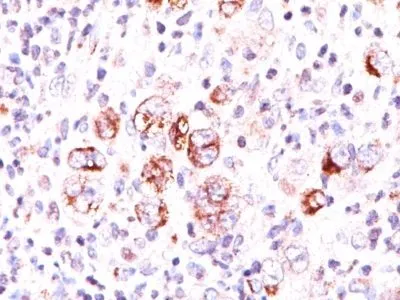

- Applications: IHC, FFPE (verified) | WB (verified)

- Validated Applications: IHC, FFPE, WB

- Positive Control: Jurkat, K562, HL-60, or HeLa Cells. Reed-Sternberg cells in Hodgkin's lymphoma.

- Additionnal Information: Higher concentration may be required for direct detection using primary antibody conjugates than for indirect detection with secondary antibody|Immunofluorescence: 0.5-1 ug/mL|Immunohistology formalin-fixed 0.5-1 ug/mL|Staining of formalin-fixed tissues requires boiling tissue sections in 10 mM Tris with 1 mM EDTA, pH 9.0, for 10-20 min followed by cooling at RT for 20 minutes|Flow Cytometry 0.5-1 ug/million cells/0.1 mL|Western blotting 0.5-1 ug/mL|Optimal dilution for a specific application should be determined by user